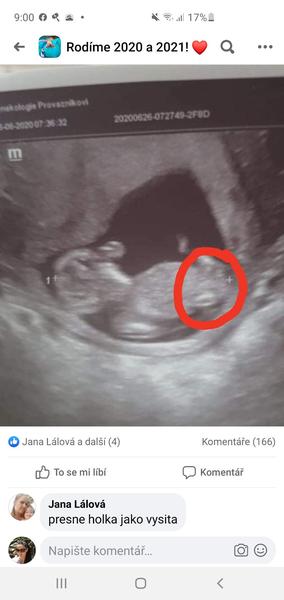

Ahojte 😊 tipnete si prosím pohlaví? Fotka je z 12+2 😊

Ještě tu mám jednu fotku 😃